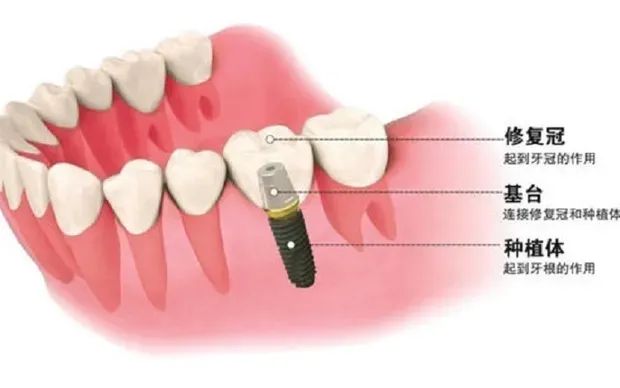

种植牙,也叫人工种植牙。通俗地说,就是将人工材料制成的种植体植入缺牙部位的牙槽骨中,再套上牙冠的过程。所以,种植牙种的并不是“螺丝钉”,是长得像螺丝钉的纯钛人工种植体,主要是用其来充当牙齿牙根的。

一颗种植牙分为三个部分:种植体+基台+牙冠。流程分为四个部分:术前准备+植入种植体+连接基台+后期修复(制作牙冠并戴入、冠体修复)。